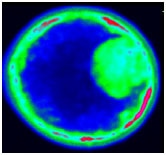

The XploRA INV also offers the option to integrate the unique scanning capabilities of HORIBA’s patented DuoScan for rapid spectroscopic multichannel Raman imaging, as well as the new 3D FCI (Fast Confocal Imaging) module, which allows ultra-fast fluorescence imaging for visualisation and verification.

White light image (left), fluorescence FCI image (center) and hyperspectral fluorescence image (right) images of a bovine embryo after staining with Nile Red, acquired on the XploRA INV. The hyperspectral image illustrates the stain in different polarity states. Data courtesy of Prof. Igor Chourpa, Université de Tours, France.